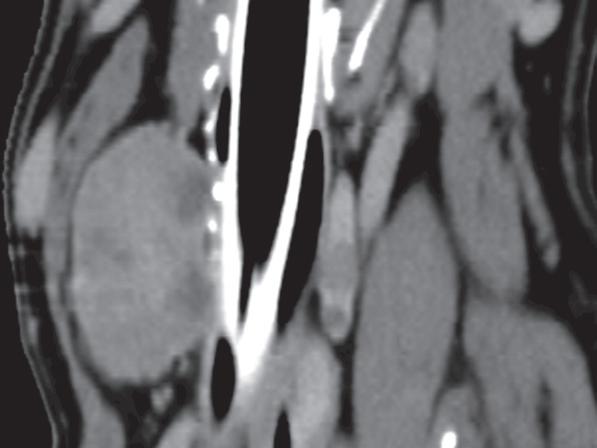

Rycina 1.11.6. Rak tarczycy i gruczolak tarczycy (pies) TK

Badanie wykonano u 12-letniej, kastrowanej samicy owczarka australijskiego z prawostronną masą w dobrzusznej części szyi. Badanie USG wykazało dużą, litą, unaczynioną masę w obrębie prawego płata tarczycy (a) oraz mniejszą, hipoechogeniczną masę w obrębie lewego płata (b). Obrazy TK przed i po podaniu środka kontrastowego (c–f) ułożone od doczaszkowych do doogonowych ukazują dużą, prawostronną, jednorodnie wzmacniającą się masę (c–f – duża strzałka) z niewyraźną granicą dobrzuszną oraz pozatorebkowym szerzeniem się i rozlanym wzmocnieniem pokontrastowym przyległych tkanek (e, f – grot strzałki). W obrazie bardziej doczaszkowym widoczny jest prawidłowy lewy płat (c, e – mała strzałka), natomiast w obrazie bardziej doogonowym jest on powiększony i ma niższą gęstość, niż można by oczekiwać, co sugeruje obecność drugiej, mniejszej masy (d, f – mała strzałka). W obrazach reformowanych wzdłuż osi długiej widać dwa małe guzki w lewym płacie (h – małe strzałki). Wyniki obrazowe potwierdzono podczas zabiegu (i, j – strzałki). Biopsja wycinkowa wykazała prawostronnego raka tarczycy z naciekaniem pozatorebkowym oraz lewostronnego gruczolaka tarczycy